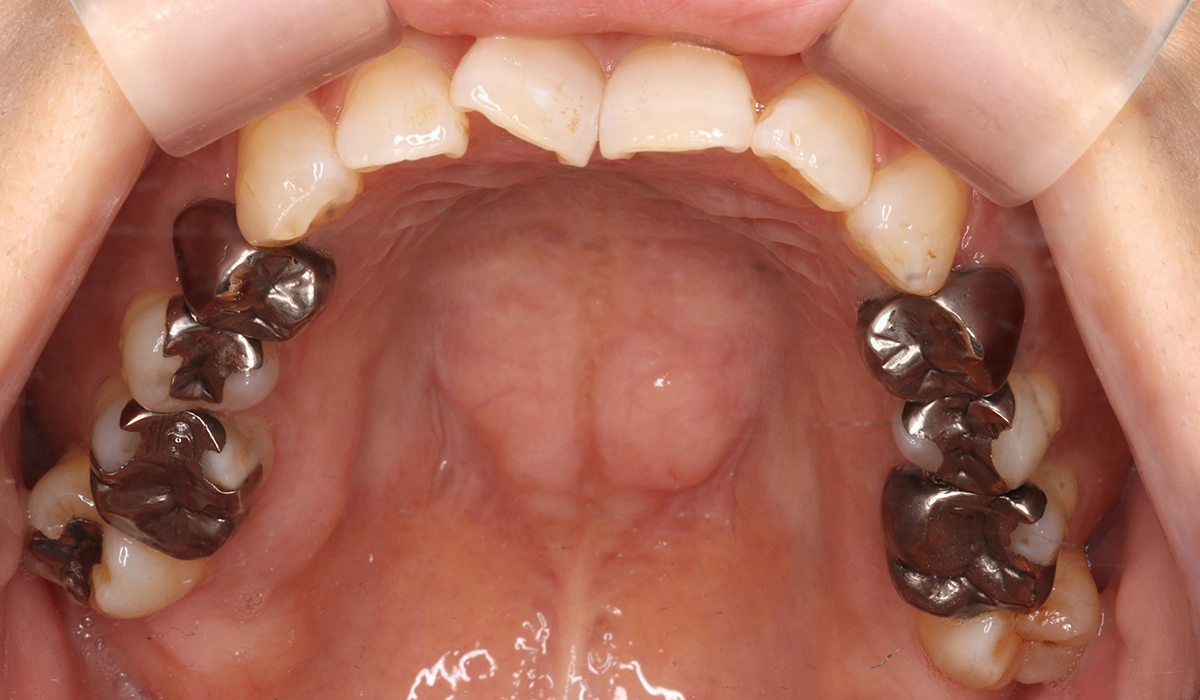

術前:上顎